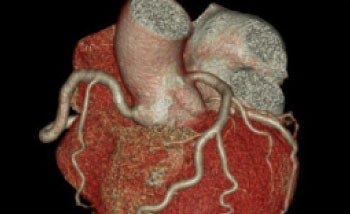

冠動脈CT

造影剤を用いて撮影することにより、心臓を栄養している動脈(冠動脈)の狭窄や閉塞によって起こる、狭心症の評価や予防に有用です。

VR表示